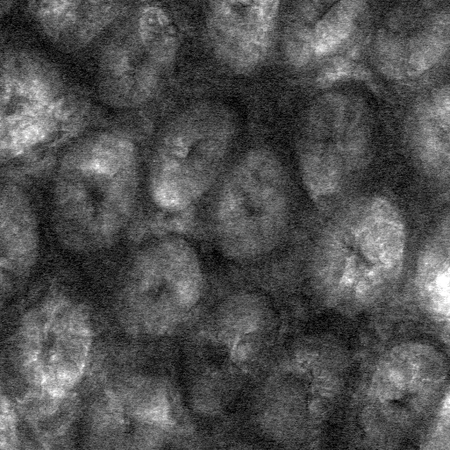

Performing their experiments in mice, the team tested the effects of polymers, which include dietary fiber as well as therapeutics such as medicines for constipation. The researchers fed some mice a diet rich in polymers and others (the controls) a polymer-free diet. Using a technique called confocal reflectance microscopy they measured the thickness of the gut gel and the degree to which the gel was compressed as a result of the consumed polymers. Mice given a high-polymer diet, they found, had a more compressed gel layer.

"The gel is like a sponge with holes that let material through," says the paper's lead author, Sujit Datta, a postdoctoral scholar in the laboratory of Rustem Ismagilov, Ethel Wilson Bowles and Robert Bowles Professor of Chemistry and Chemical Engineering. "We are seeing that polymers, including dietary fiber, can compress the gel, potentially making the holes smaller, and we think that this might offer protective benefits," Datta adds.

In addition, the researchers applied different kinds of polymers—including dietary fibers like pectin, found in apples—directly to the gel lining to test its response. All of the polymers tested compressed the gel layer.